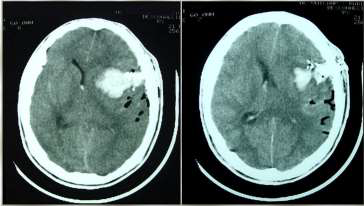

Caso clínico 3 para as questões 27 e 28.

Criança feminina, 04 anos, é encaminhada de Unidade de Pronto Atendimento (UPA) de Olinda-PE com história de cefaleia acompanhada de vômitos, inapetência e sonolência há 03 dias, sendo solicitado parecer da neurocirurgia. Ao exame: ECG Pediátrica de 13 (Resposta Ocular = 3 + Resposta Verbal = 4 + Resposta Motora = 6), isocórica e RFM lentificado bilateralmente, mobilizando todos os membros e reflexos presentes e simétricos.

Seguem, abaixo, as imagens de TC de crânio sem e com contraste da paciente, com índice de Evans de 0,41.

Pelas imagens mostradas, qual o mais provável diagnóstico e o objetivo do tratamento para a paciente?

Caso clínico 3 para as questões 27 e 28.

Criança feminina, 04 anos, é encaminhada de Unidade de Pronto Atendimento (UPA) de Olinda-PE com história de cefaleia acompanhada de vômitos, inapetência e sonolência há 03 dias, sendo solicitado parecer da neurocirurgia. Ao exame: ECG Pediátrica de 13 (Resposta Ocular = 3 + Resposta Verbal = 4 + Resposta Motora = 6), isocórica e RFM lentificado bilateralmente, mobilizando todos os membros e reflexos presentes e simétricos.

Seguem, abaixo, as imagens de TC de crânio sem e com contraste da paciente, com índice de Evans de 0,41.

Como se calcula o índice de Evans que foi de 0,41 e o que se fazer pela urgência nesse caso, respectivamente?